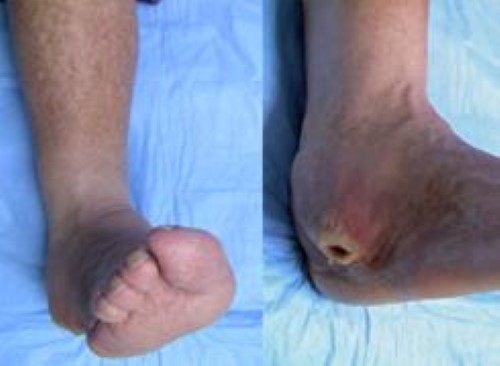

chronic sore on the ankle

(Left) This patient with Charcot of the ankle has developed a deformity that places abnormal pressure on the outside of the ankle. (Right) This pressure has led to the development of a chronic sore (ulcer) that can be extremely difficult to treat.